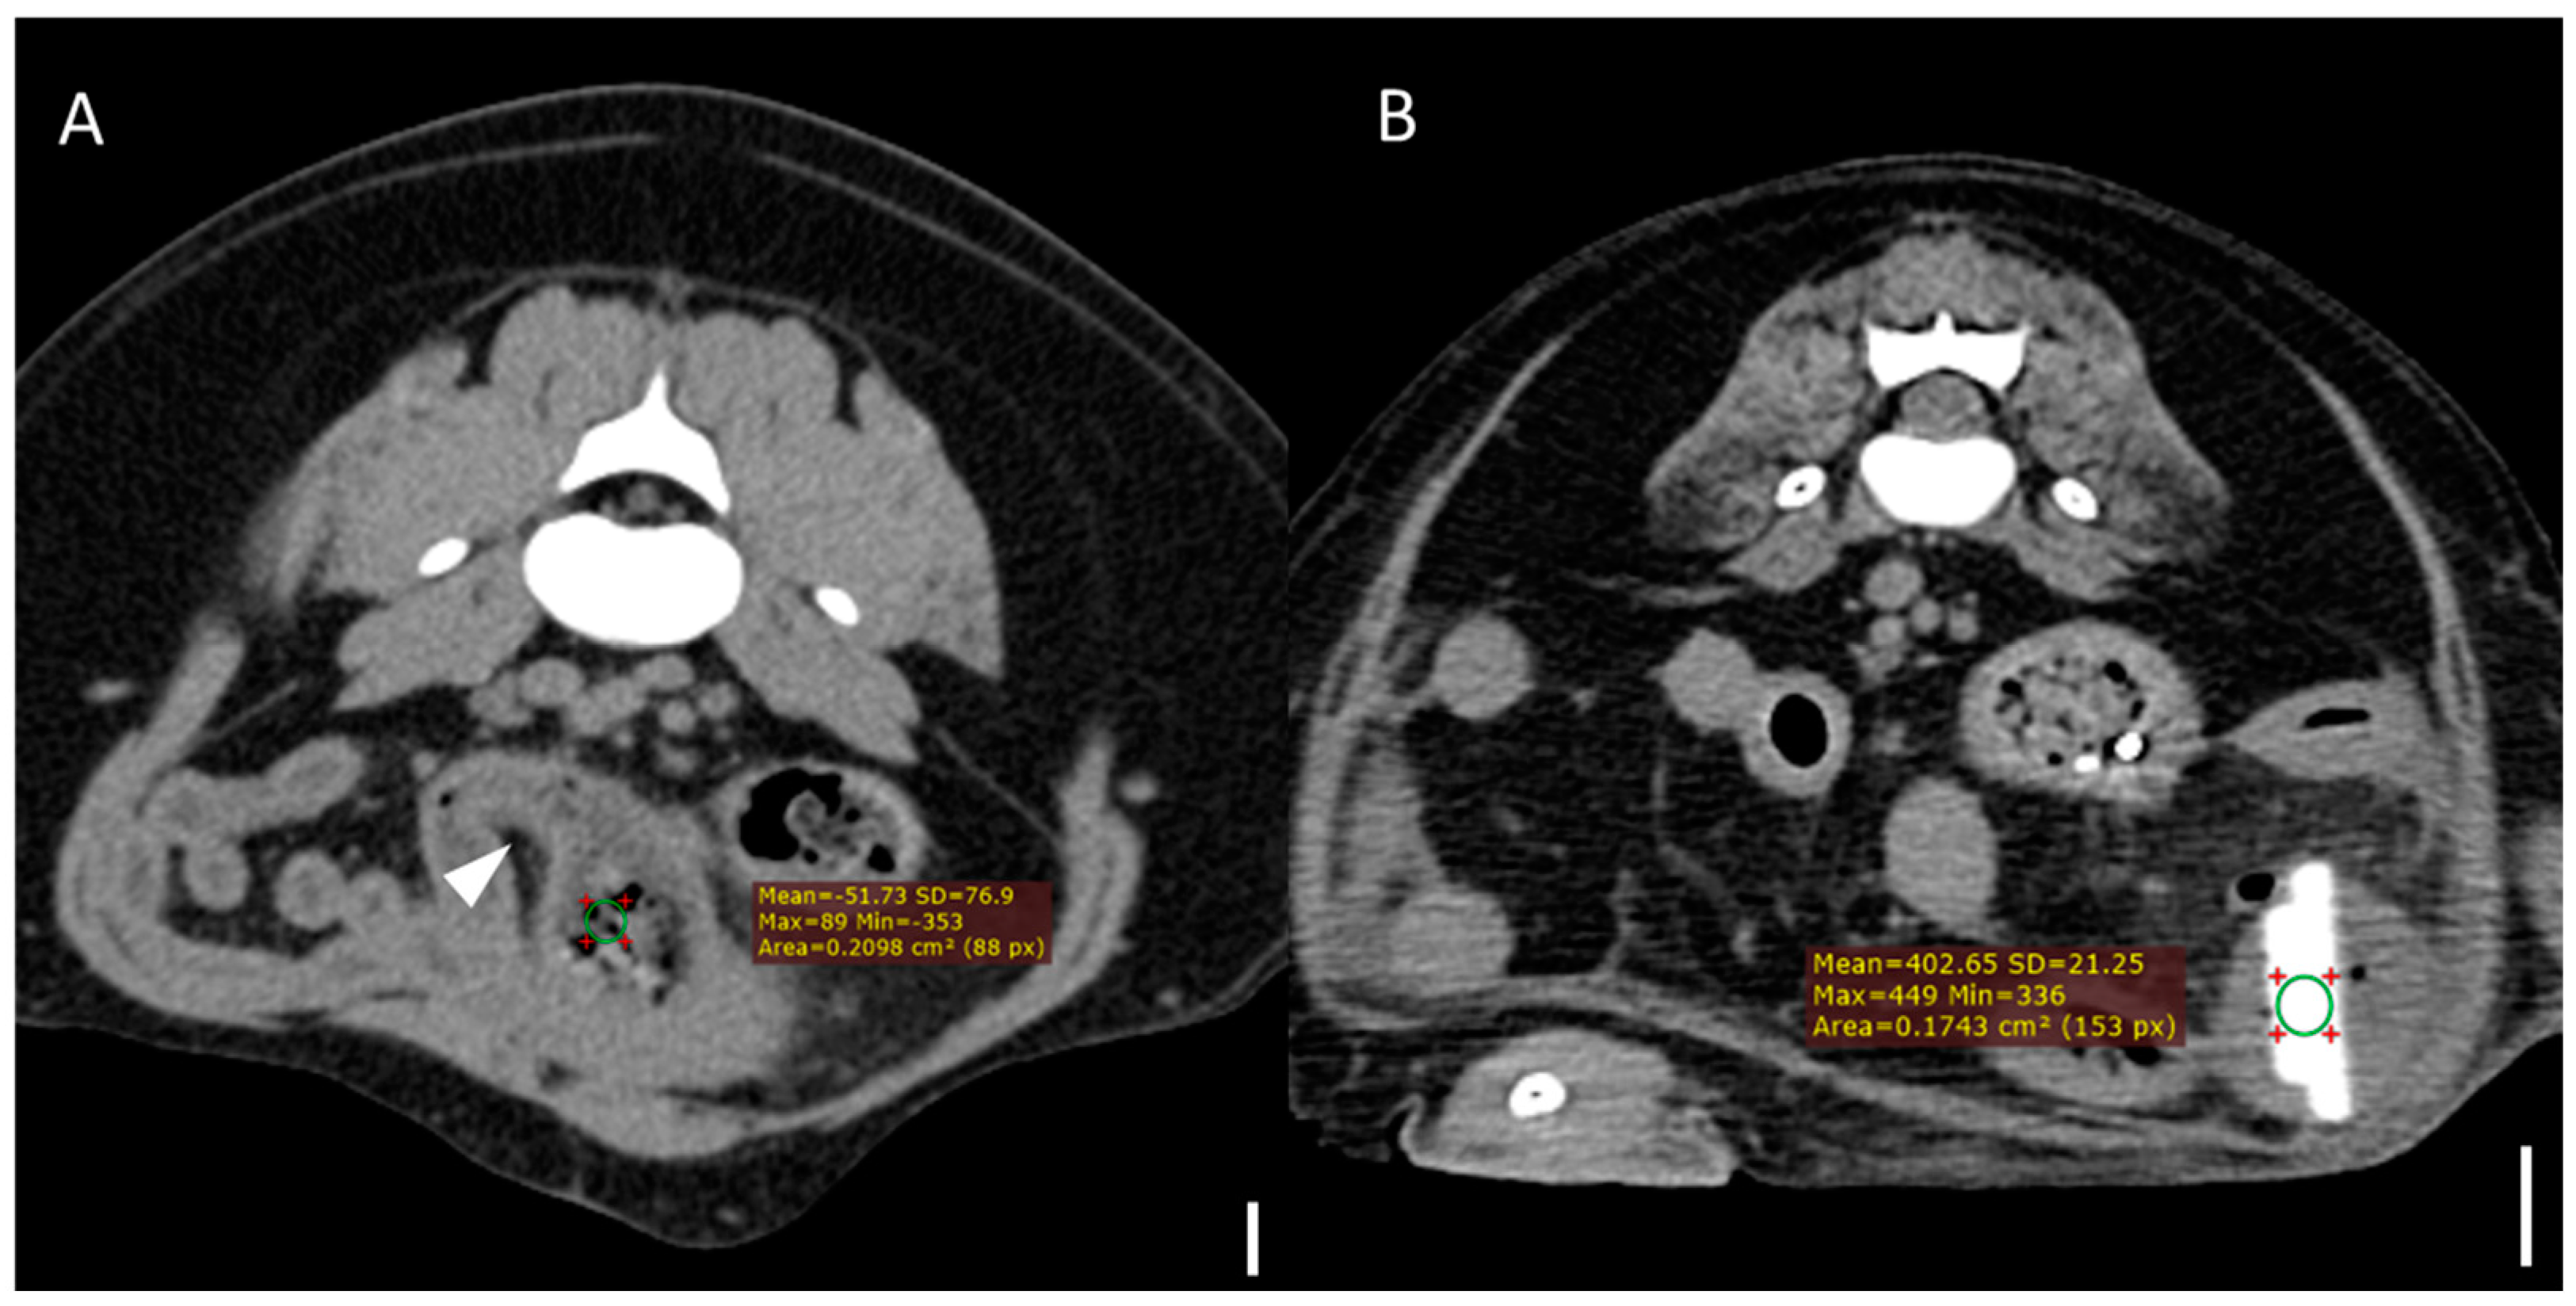

Figure 2. Representative CT images demonstrating attenuation measurement using region-of-interest (ROI) analysis (scale bar equals 1 cm) (A) Transverse CT image from a case of bezoar obstruction. The arrowhead indicates the presumed site of obstruction in the jejunum. A circular ROI (area = 20.98 mm2) was manually placed over the obstructive material, yielding a mean attenuation value of –51.73 Hounsfield units (HUs). (B) Transverse CT image from a case with a distinct foreign body (stone), where the ROI (area = 17.43 mm2) was placed directly on the foreign body, yielding a mean attenuation of 402.65 HUs. All measurements were performed on precontrast images using manually drawn circular ROIs, with consistent size (15–20 mm2) across cases.

Computed tomography (CT) images were evaluated using multiplanar reconstruction tools provided by Radiant software. In most cases, postcontrast images were available; however, precontrast images were used specifically for attenuation value (HU) measurements of foreign bodies. CT evaluations included both qualitative and quantitative assessments. Qualitative CT criteria included the presence of a transition zone, defined as an area where the bowel abruptly changes from dilated to normal; collapsed segments [18] (Figure 1); the identification of the boundary between foreign bodies and intestinal contents; and the location of the foreign bodies. Gastric foreign bodies were excluded from transition zone evaluation, as the stomach does not exhibit a discrete diameter change consistent with the transition zone definition, which applies specifically to small bowel obstruction [19]. The presence of a boundary between the foreign body and the small intestinal contents was also evaluated through multiplanar reconstruction. The location of foreign bodies was categorized as follows: stomach, duodenum (the portion of the intestine extending aborally from the stomach to the proximal jejunum situated to the left of the mesenteric root), jejunum (the section of intestine between the aborad broad portion of the duodenum and ileum), ileum (the distal portion of the small intestine located abroad to ileocolic junction), and multisegmental involvement [4]. The quantitative CT evaluation criteria included the mean, maximum, and minimum attenuation values of the foreign bodies; the ratio of the small intestinal diameter between the most distended segment proximal (orad) to the foreign body and the adjacent collapsed distal (aborad) segment [15], (Figure 1); the number of complications identified on CT imaging caused by foreign bodies; and the severity of small intestinal dilation caused by foreign bodies normalized to vertebral measurements (SI/L5 in dogs and SI/L2 endplate in cats). Attenuation value measurements were conducted on precontrast images, with values measured in Hounsfield units (HUs) within manually drawn circular regions of interest typically 15–20 mm2 in area (Figure 2). For distinct foreign bodies, ROIs were placed directly within the visible object. In cases of bezoars, measurements were taken from the area presumed to contain the foreign material, based on the site of obstruction identified on CT. ROIs were carefully positioned to avoid intraluminal gas or the adjacent intestinal wall, and three measurements were averaged for each case. Complications identified on CT imaging included signs of peritonitis (e.g., increased mesenteric density and peritoneal fluid) [20], rupture of the bowel wall, involvement of foreign bodies across multiple segments [21], foreign bodies affecting organs beyond the gastrointestinal tract (Figure 3), signs of bowel wall ischemia or hypoxic changes, and the degree of obstruction (complete or partial). The severity of small intestinal dilation was classified as normal (SI/L5 < 1.6 in dogs, SI/L2 < 2.0 in cats), mild (SI/L5 1.6–2.0 in dogs, SI/L2 2.0–2.5 in cats), moderate (SI/L5 2.0–2.4 in dogs, SI/L2 2.5–3.0 in cats), or severe (SI/L5 > 2.4 in dogs, SI/L2 > 3.0 in cats) [5,16,17,22]. This measurement was applied exclusively to small intestinal segments; gastric foreign bodies were excluded from this assessment.

The quantitative CT findings are summarized in Table 5. Compared to distinct foreign bodies, bezoars exhibited significantly lower attenuation values across all three measures. Median values in the bezoar group were –61.2 HUs (average), 53 HUs (maximum), and –364 HUs (minimum), while the distinct foreign body group showed 166.8 HUs, 254.5 HUs, and 139.5 HUs, respectively (p < 0.001, p < 0.001, and p = 0.004).